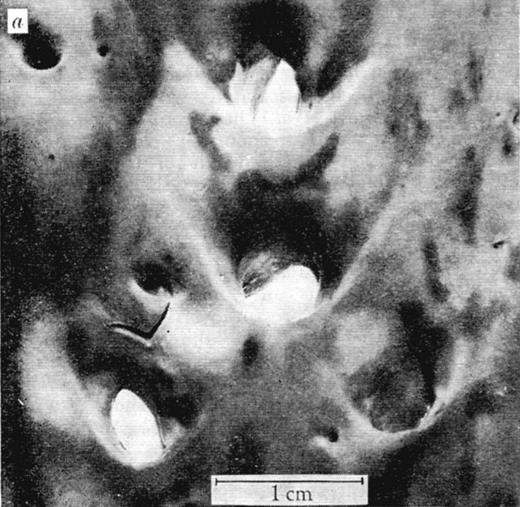

Major decisive influences on the sites of leukocyte transmigration, most notable in arteries, are the local characteristics of blood flow.41 In the 1960s, the arterial distribution of atherosclerotic lesions, formed by transmigrating monocytes accumulating lipids, was found not to be random, and the influence of blood mechanics was considered. Caro et al proposed the hypothesis that “… fluid mechanics has a controlling and inhibiting (or retarding) effect rather than a causative one” on atherogenesis.42 By thorough quantitative evaluation of lesion location within arterial bifurcations (Figure 4) and flow modeling, the authors determined that there were fewer lesions in the areas of arterial bifurcations where shear rates are locally high and laminar and more lesions on the opposite side that experiences lower shear and turbulent flow. Interestingly, the authors proposed that increasing cardiac output through exercise might retard the development of atheroma.42

View of human aorta stained with Sudan III for fat deposits/atheroma (dark stains) from the intimal side. Outer wall branches (experiencing disturbed flow) of the celiac, superior mesenteric, and renal arteries show more extensive staining than the inner walls where shear rates are high and laminar. Reproduced with permission from Macmillan Publishers Ltd.42